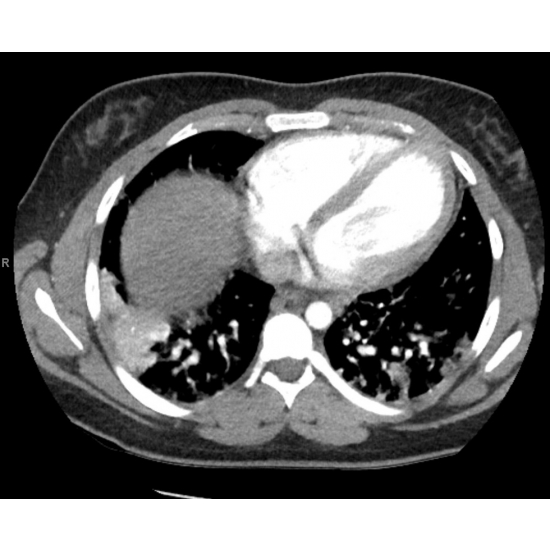

CT Angiogram Pulmonary: Diffuse multifocal consolidations concerning for multifocal pneumonia with mild interstitial pulmonary edema. Case Photo #4 and Case Photo #5